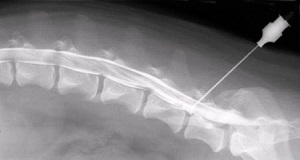

Миелография (контрастная спондилография) - метод рентгенографического исследования спинного мозга с использованием контрастного вещества. При обычном обзорном рентгене на снимке видны контуры только костной ткани позвоночника. Применение контрастного вещества позволяет увидеть также контуры нервных тканей - спинного мозга и спинномозговых нервов.

Проведение миелографии

В качестве контрастного вещества чаще всего используется омнипак (ойгексол). Препарат вводится путем прокола оболочки спинного мозга (как, например, при эпидуральной анестезии). Процедура проводится под наркозом, в стерильных условиях операционной. Контрастное вещество может вводиться в поясничном отделе позвоночника или в области большого затылочного отверстия (субокципитальная пункция), часто показано одновременное введение контраста и люмбально (в области поясницы) и окципитально (в области затылочного отверстия). Субокципитальная пункция более опасна - есть вероятность (порядка 1-2%) повреждения сосуда, что приводит к отеку спинного мозга и дыхательному и сердечно-сосудистому параличу.